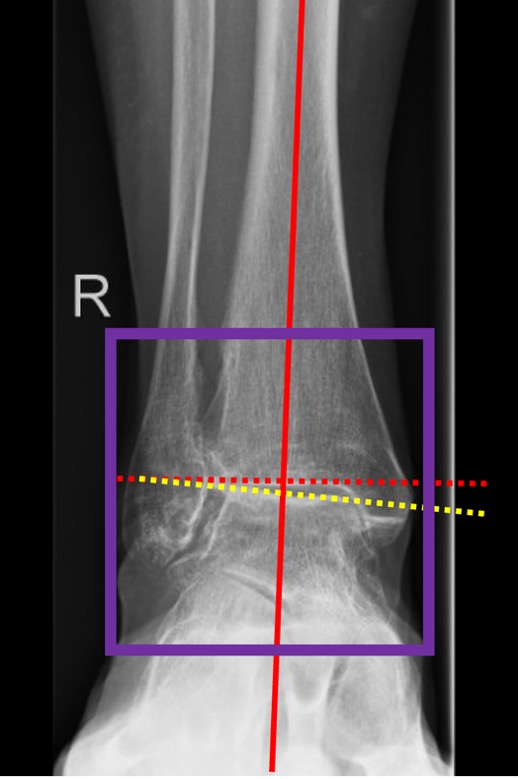

- angles are measured using a weight-bearing mortise view

- coronal plane parameters:

- medial distal tibial angle (MDTA), also called the tibial articular surface angle (TAS)

- tibio-talar surface angle (TTS)

- tibio-talar angle (TTA)

Figure 5. Measuring the deformity

- MDTA (TAS) is crucial for quantifying the supramalleolar deformity (Fig. 3)

- TTA normally defines the centre of rotation of angulation (CORA)

- Talar tilt should be used for quantitative assessment of an intra-articular deformity in the coronal plane. It is defined as the difference between the MDTA and the TTA

Talus tilt (TTA) = TTS – mDTAA

- Values of >4° are considered to be pathological